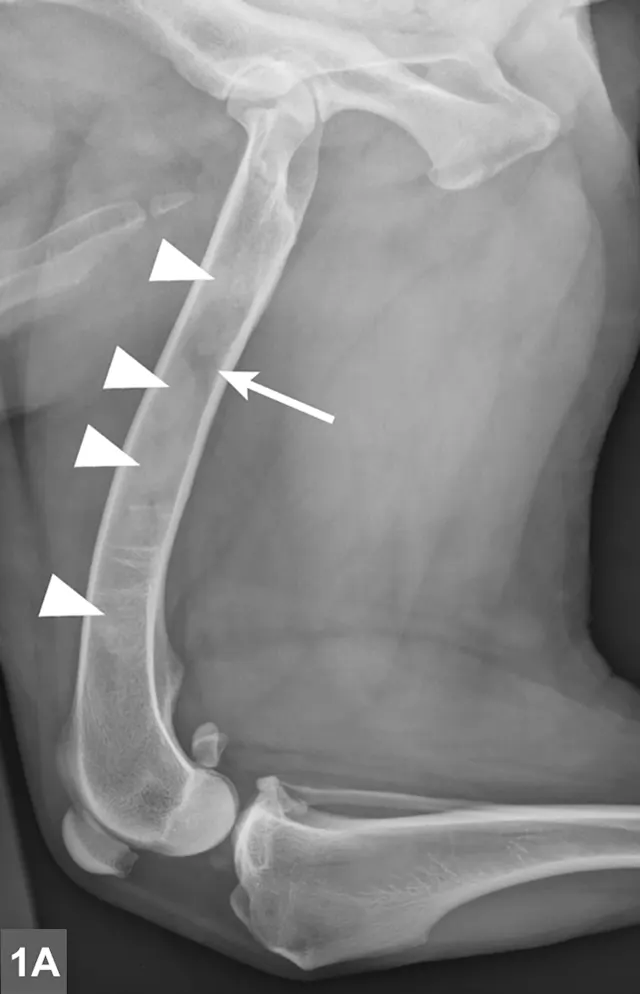

FIGURE 1A

Lateral radiographic projections of the femur (A) and ulna (B, next slide) in dogs with early signs of panosteitis. Note the radiolucency around the nutrient foramen (arrows) and increased opacity within the medullary canal (arrowheads) in both cases.